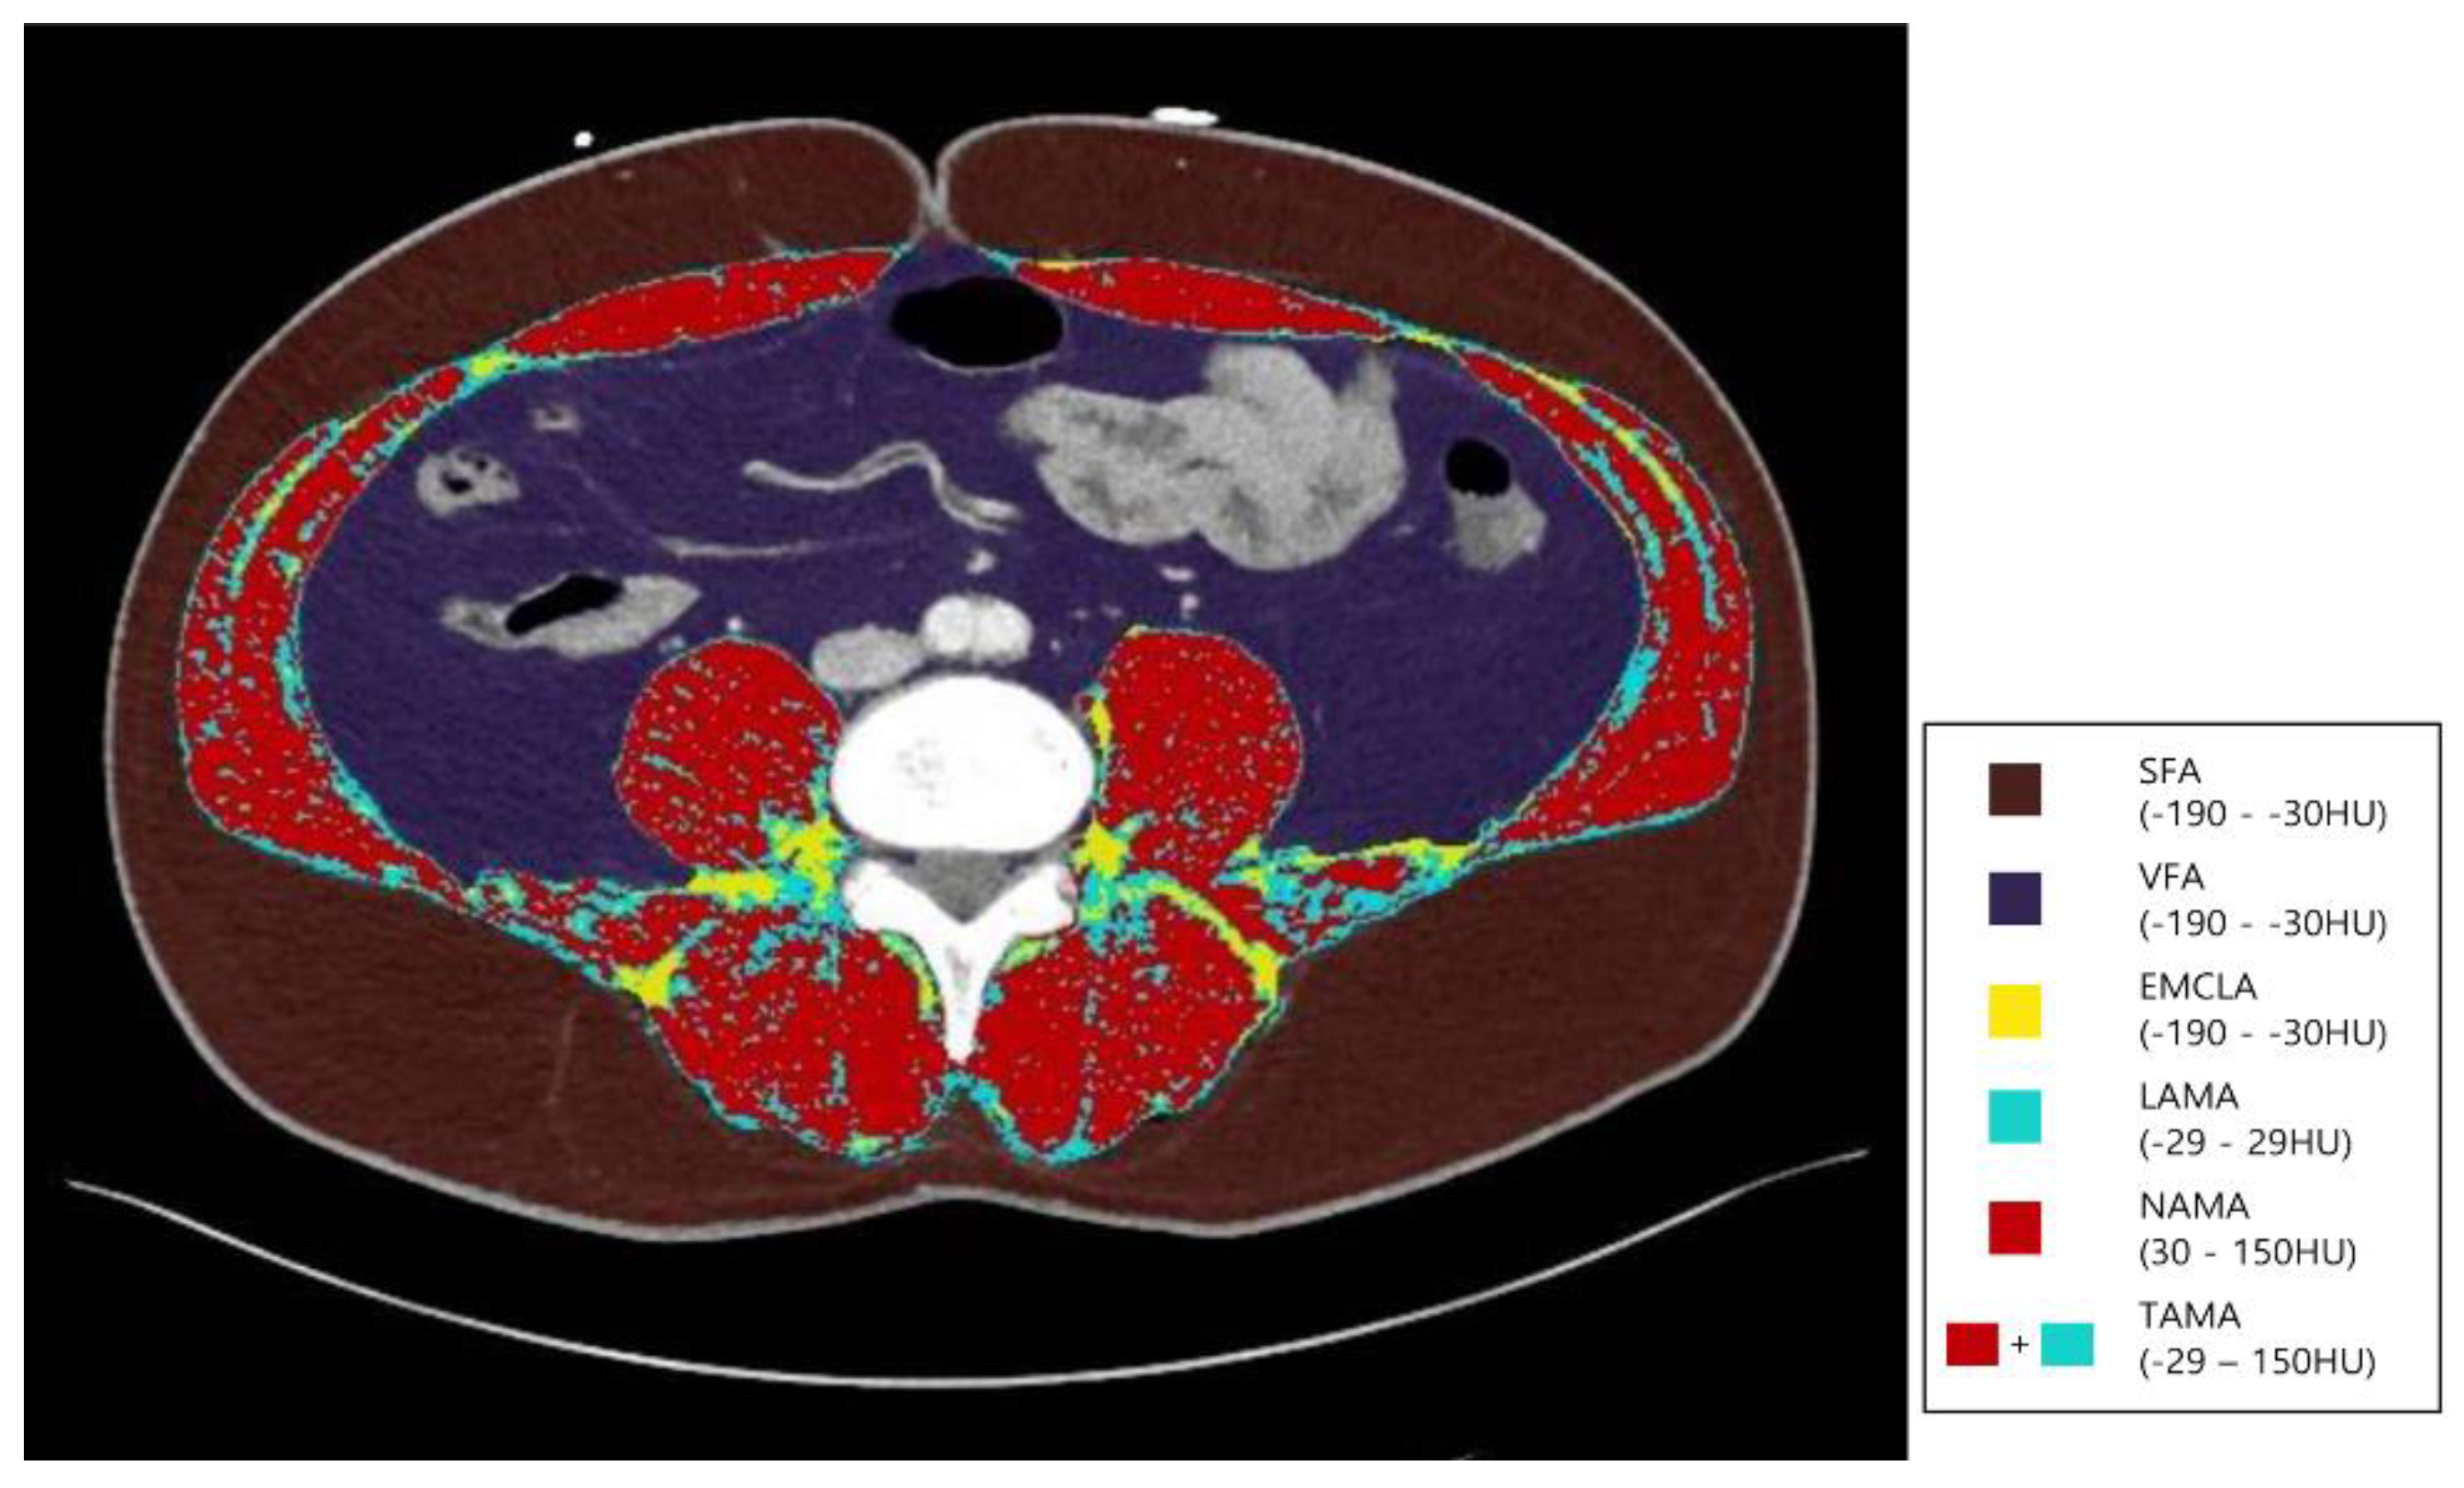

2.3. APCT Image Acquisition and Analysis